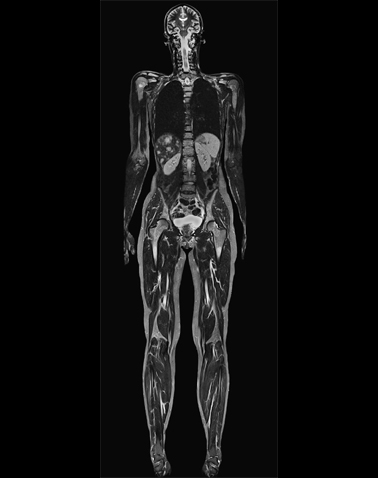

Dieses moderne bildgebende Verfahren ermöglicht umfassende und diagnostisch wichtige Aussagen über die arteriellen Gefäße. Untersucht werden vor allem die Becken-Bein-Gefäße, die Bauchgefäße und die Gefäße im Hals- und Kopfbereich. Nach Injektion eines nicht-jodhaltigen Kontrastmittels kann dessen Weg durch die jetzt stark kontrastierten Adern verfolgt und zwei- und dreidimensional dargestellt werden. Dank moderner MRT-Spulentechniken können auch lange Gefäße mit einer einzigen Aufnahme erfasst werden.

Becken- und Beingefäße

Ganzkörper-Angiografie